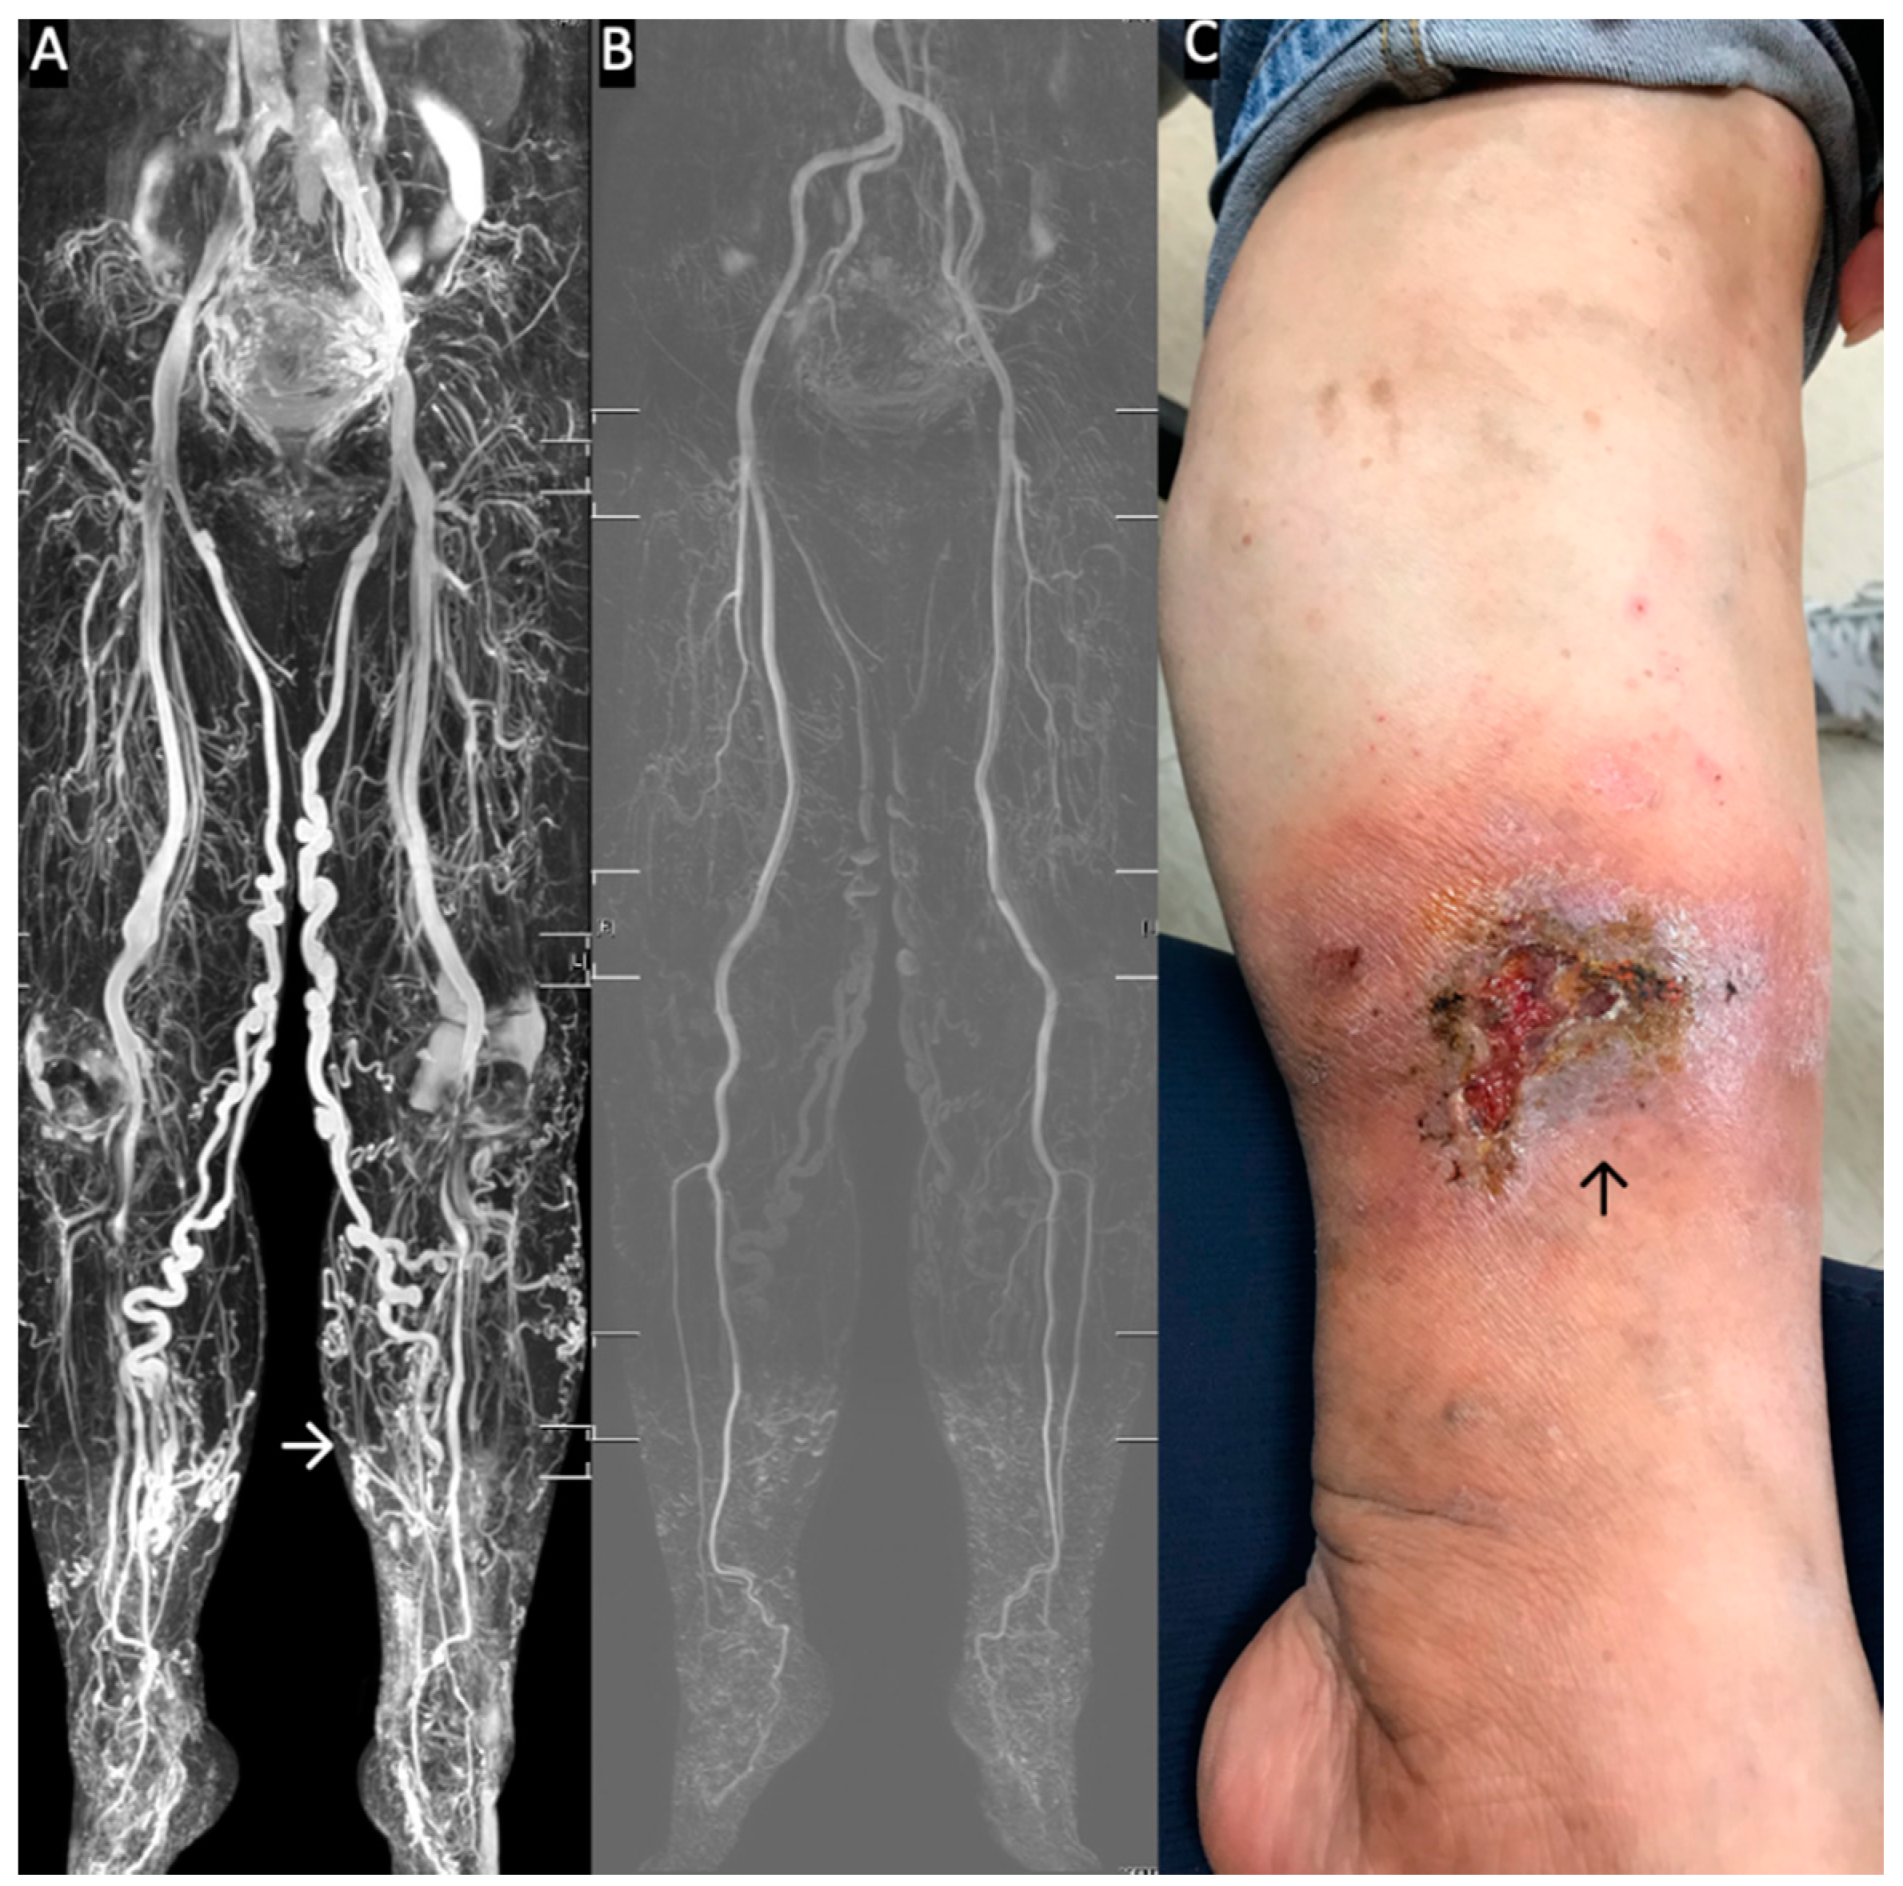

Figure 2.

Standard Triggered angiography non-contrast-enhanced (TRANCE)-magnetic resonance imaging (MRI) evaluation for patients with stasis leg ulcers. (A) Full TRANCE-MRI. The TRANCE-MR image of the venous system clearly shows the tortious great saphenous vein (GSV) in both legs. The white arrow indicates the stasis leg ulcer. (B) The TRANCE-MRI can also identify the arterial system. There is no need for radiation or injection of contrast medium. (C) Stasis leg ulcer of the gaiter area. This wound healed one month later, after truncal ablation of the left GSV.